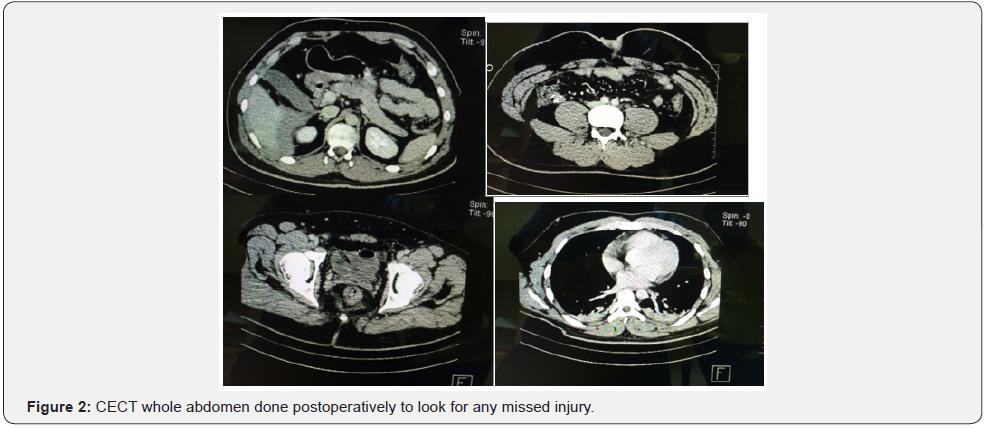

His intraoperative findings were approximately 500-600ml blood present in peritoneal cavity, thickened swollen appendix present (not perforated) echymotic macular spots present over bladder and rectum, no obvious bleeding/blood staining present in peritoneum, mesentry or retroperitoneum, no bowel or any solid organ injury noted. Postoperatively repeated haemoglobin and other blood tests were done which were within normal limits without any significant fall in haemoglobin. His CECT whole abdomen done postoperatively to look for any missed injury (Figure 1 & 2).